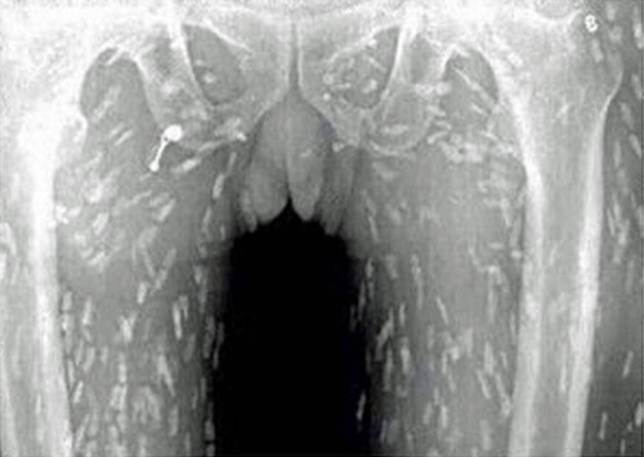

Um homem morador da província de Guangdong, na China, parou no hospital com dores no estômago após comer muito sashimi.

No local, ele foi submetido a um raio-X, que revelou que havia centenas de tênias rastejando por suas entranhas, depois que ele ingeriu a comida contaminada pelo parasita.

Para a agonia (e atenção) de todos os adoradores da comida japonesa, a imagem foi divulgada na internet.